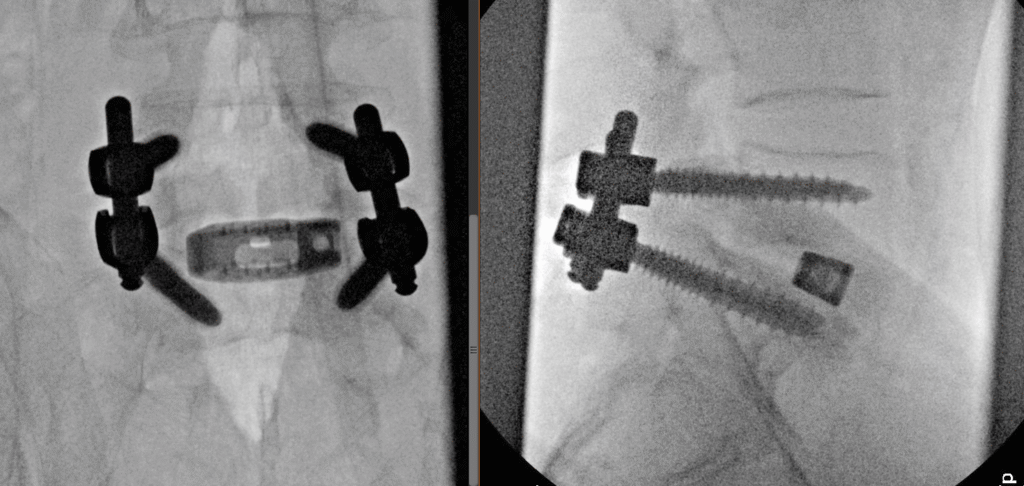

Transforaminal Lumbar Spine Fusion